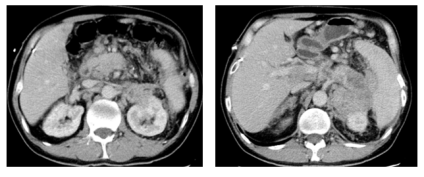

(2024年02月)8周期化疗后,复查CT评效:肝多发转移,较前减少缩小,胰腺区,左肾前,脾内侧多发转移较前稍缩小,肝门区,肠系膜内及腹膜后淋巴结较前明显缩小,部分消失。评效维持PR。

image.png

图3 8周期化疗后复查CT结果